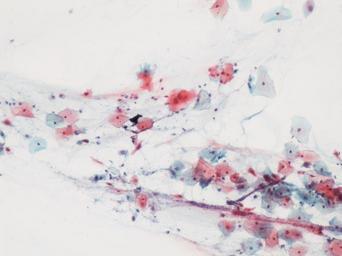

Keywords: lesión intraepitelial escamosa de bajo grado lesiónintraepitelialescamosadebajogrado citología de cuello uterino citologíadecuellouterino citología exfoliativa ginecológica citologíaexfoliativaginecológica citología de cribado citologíadecribado citología anatomía patológica anatomíapatológica bethesda 2001 bethesda2001 osuna cérvix uterino cérvixuterino hpv españa screening lsil enfermedades de transmisión sexual enfermedadesdetransmisiónsexual imágenes de citología ginecológica imágenesdecitologíaginecológica papanicolaou test de papanicolaou testdepapanicolaou tinción de papanicolaou tincióndepapanicolaou snow drawing Células con núcleo y citoplasma aumentado de tamaño, núcleos irregulares, como plumosos, tendencia al color naranja de muchas células, halos en algunos casos, núcleos dobles en otros, algunos núcleos hipercromáticos. Células con núcleo y citoplasma aumentado de tamaño, núcleos irregulares, como plumosos, tendencia al color naranja de muchas células, halos en algunos casos, núcleos dobles en otros, algunos núcleos hipercromáticos.